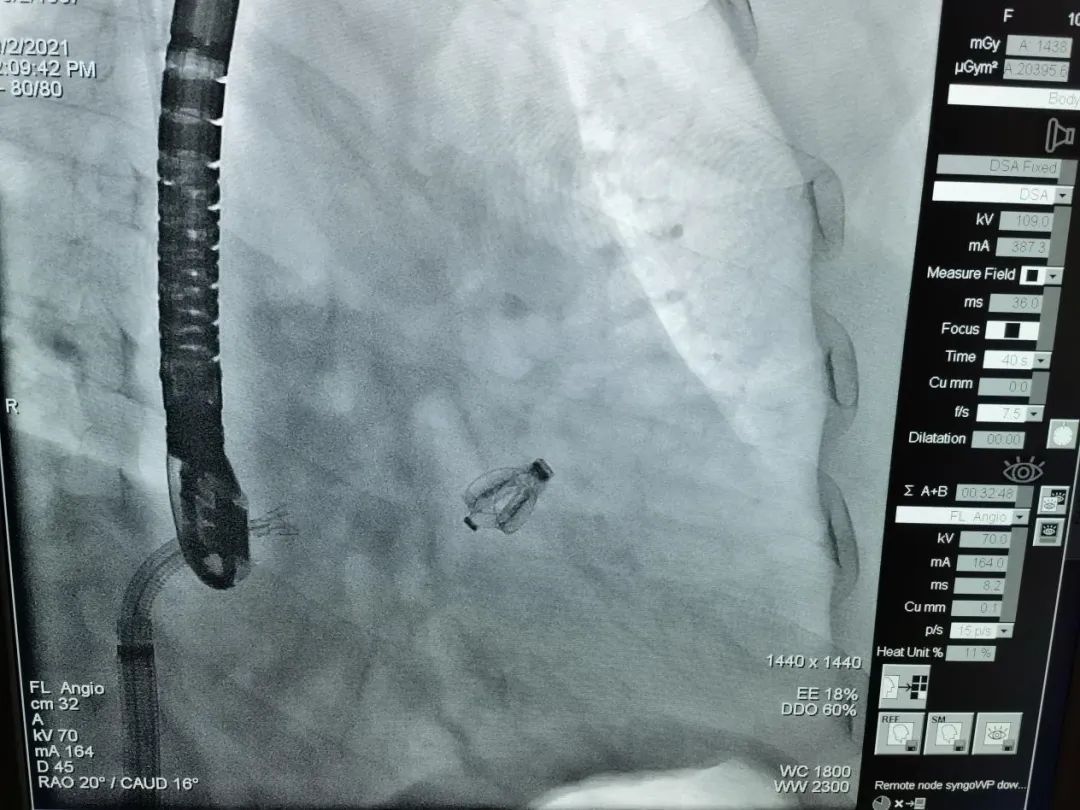

本次手术的患者是一名高龄女性,经超声心动图评估为重度三尖瓣反流,临床症状符合手术指征,经董念国教授团队多学科评估决定为患者行经导管三尖瓣夹合器钳夹术。手术由协和医院瓣膜中心核心成员尚小珂、陈澍、钟禹成教授联袂,方凌云医生经食道超声心动图引导下,使用Neoblazar™经导管三尖瓣夹合器,经股静脉穿刺,送入导丝建立右心房通路,使用扩张器对穿刺口进行扩张,送入22F可调弯指引鞘组,在右心房调整双层控弯导管,使夹合器置于三尖瓣前叶与膈叶间反流最大区域,在DSA与超声双重指引下跨瓣进行瓣叶的捕获与夹合,夹合后成功解离夹合器,输送系统顺利撤出体外,术后即刻超声心动图评估三尖瓣反流降至轻度,手术取得圆满成功。

DSA下夹合器形态